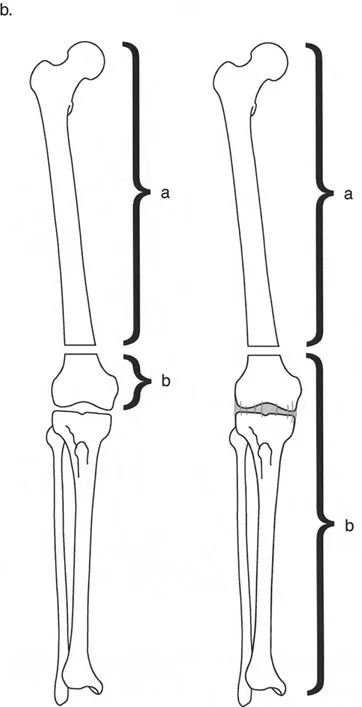

- قاعدة قطع العظم 1: عندما يمر قطع العظم ومحور تصحيح الانحراف (ACA) كلاهما عبر مركز دوران الانحراف (CORA)، فإن نهايات العظم ستنحرف دون ترجمة (انزياح). يتم استعادة المحور الميكانيكي، وتظل نهايات العظم متقاربة تمامًا، مما يخلق تصحيحًا كلاسيكيًا "إسفينيًا مفتوحًا" أو "إسفينيًا مغلقًا".

- قاعدة قطع العظم 2: عندما يمر محور تصحيح الانحراف (ACA) عبر مركز دوران الانحراف (CORA)، ولكن يتم إجراء قطع العظم على مستوى مختلف (غالبًا بسبب ضعف جودة العظم عند CORA أو مشاكل في الجلد)، فإن نهايات العظم ستنحرف وتخضع لترجمة محسوبة ومقصودة لإعادة محاذاة المحور الميكانيكي.

- قاعدة قطع العظم 3: (للاكمال) عندما يمر قطع العظم عبر مركز دوران الانحراف (CORA)، ولكن يتم وضع محور تصحيح الانحراف (ACA) خارج CORA، سيتم إنشاء تشوه ترجمة جديد، وهو خطأ شائع في وضع المفصلات غير المخطط له جيدًا.

في المنشآت القريبة من المفصل، غالبًا ما نعتمد على قاعدة قطع العظم 2. نظرًا لأنه لا يمكننا قطع العظم بأمان عند خط المفصل تمامًا (مركز دوران الانحراف CORA)، فإننا نقطع العظم في مستوى أدنى في منطقة الميتافيسيس. بعد تحقيق التصحيح الزاوي عبر المفصلات (محور تصحيح الانحراف ACA)، يتم إعادة محاذاة خطوط المحور الميكانيكي بشكل مثالي، ولكن نهايات العظم في موقع قطع العظم تتحرك بالنسبة لبعضها البعض.